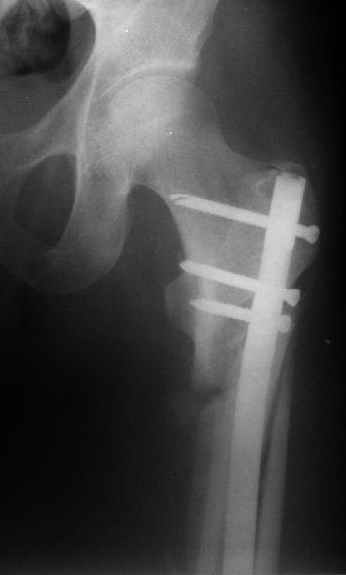

Женя, эта картинка показывает не оптимальное лечение вертельных переломов в моем представлении, а особенности дизайна упомяутого фиксатора.

В частности, его возможности при фиксации переломов проксимального отдела бедра - в сравнении с другими, имеюшими лишь по одному статическому и динамическому отверстию и с кондуктором для введения 2 винтов.

Это было года 2,5 назад, мы тогда еще уточняли возможности шинирования с угловой стабильностью гвоздем с поперечным расположением винтов при переломах проксимального отдела бедра. Пациенту не пришлось приобретать намного более дорогой рекон или проксимальный гвоздь. В приложении еще несколько примеров применения того гвоздя при высоких переломах бедра, в том числе с более латеральной точкой входа. Гвоздь изгибаем для этого.